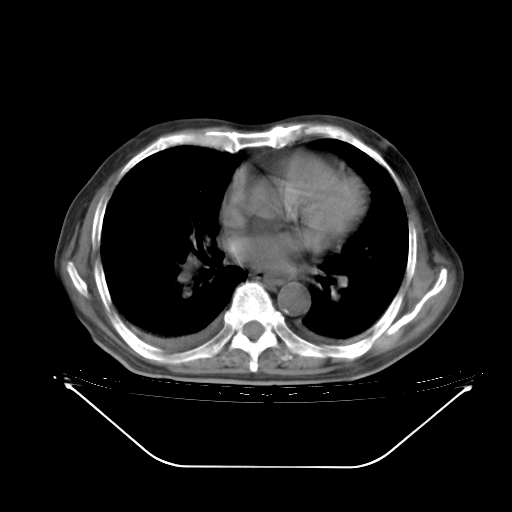

今天复查肺部CT,发现双肺广泛磨玻璃样改变。所以我把3月19日和5月9日相隔50天的肺部CT上传。请大家会诊。

2009年3月19日肺部CT片。

5月9日肺部CT(在4月27日齐鲁医院肺部CT描述部分肺组织磨玻璃样改变,12天后肺组织广泛磨玻璃样改变)